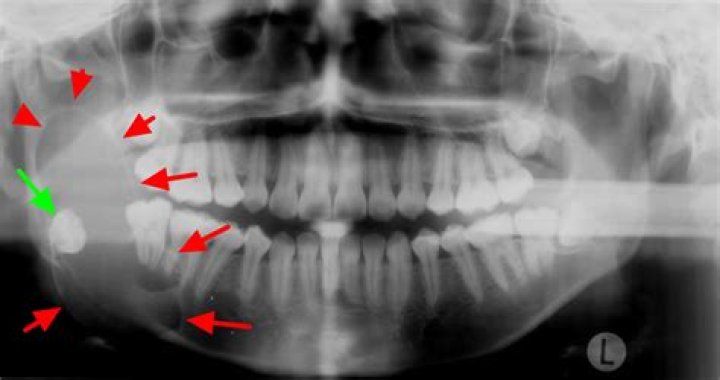

According to Worth,[4] the most common radiographic appearance of ameloblastoma is a multilocular radiolucency with a corticated border, and margins, which usually show irregular scalloping.

Ameloblastoma is characterized by an abnormal growth in the sinus area or jaw, often at the site of the third molar. The tumors or cysts may be aggressive and may spread to the nose, eye socket and skull.

Although the presence of a tooth within a lucent mass is pathognomonic for a dentigerous cyst, the aggressive features of portions of the mass and the presence of solid enhancing nodular foci were inconsistent with this type of cyst. Thus, ameloblastoma was the primary differential diagnosis.

Most OKCs showed smooth border and unilocular shape, while most ameloblastomas showed scalloped border and multilocular shape. Compared with ameloblastomas, OKCs showed greater frequency to be associated with impacted tooth, and were unlikely to cause tooth displacement and root resorption.